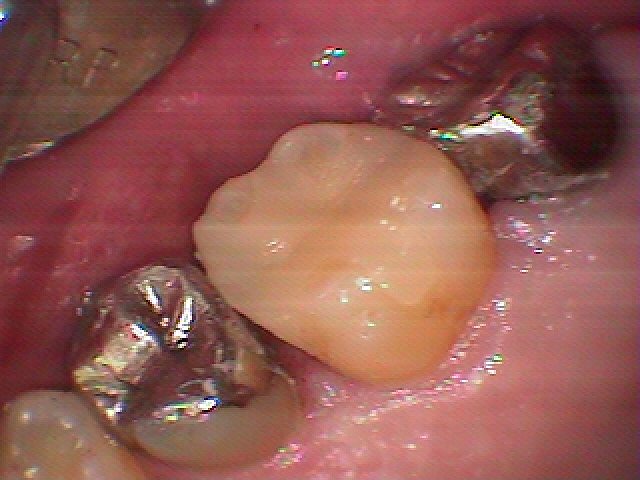

左上6番の銀歯をはずして虫歯治療へ 白いセラミックへやりお変えていきます|お知らせ |広島市安佐南区の歯科医院 左上6番の銀歯をはずして虫歯治療へ 白いセラミックへやりお変えていきます トップ お知らせ・ブログ お知らせ 左上6番の銀歯をはずして虫歯治療へ 白いセラミックへやりお変えていきます 左上6番の銀歯をはずして虫歯治療へ 白いセラミックへやりお変えていきます この歯の遠心隣接部に虫歯が存在しています 銀歯をはずした直後になります むし歯も見えます 遠心部がこのように虫歯になっています 歯科医師の見立てから検診にて判断していきます むし歯を除去していきました プライムスキャンを用いたセレックセラミックにて修復しています このようにきれいに仕上がりました 喜んでいただきました Web診療予約 初めての方へ 選ばれ続ける理由 院内設備について 歯が痛いしみる一般歯科 歯がぐらぐらする歯周病 健康な歯を保ちたい予防歯科 子供の虫歯予防をしたい小児歯科 銀歯をセラミックに審美歯科 白い歯を目指しませんか?ホワイトニング 矯正専門医がいるので安心矯正歯科 抜けた歯を補いたいインプラント・入れ歯 医院案内 スタッフ紹介 メリィハウス歯科クリニックオフィシャルホームページ ラベンダー歯科クリニックオフィシャルホームページ お知らせ・ブログ ホーム 診療科目 一般歯科 歯周病治療 予防治療 小児歯科 審美治療 ホワイトニング 矯正歯科 入れ歯・インプラント マウスピース矯正 初めての方へ 院長・スタッフ 設備紹介 医院案内・アクセス メニューを閉じる